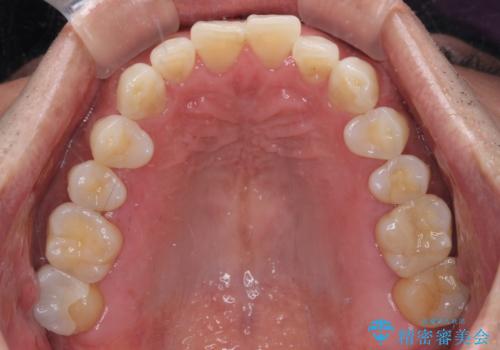

内側にある歯が干渉する 上顎前歯の部分矯正

- 上顎の前歯が内側にあり、下顎のセラミッククラウンと干渉することが気になるとのことで来院された患者様です。

上顎前歯にワイヤー装置を装着し、セラミッククラウンとは干渉しないようにしながら歯列を整えることとしました。

セラミッククラウンとの干渉はすぐに改善され、歯列も整いましたが、一方で、前歯で食事が噛みにくくなり、1年近い治療期間となりました。